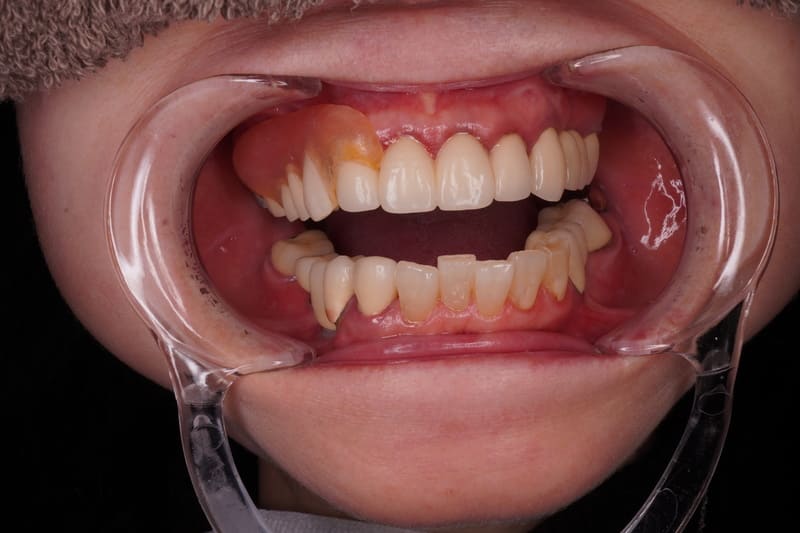

Before

After

主訴 左上のセラミックの歯の歯ぐきが下がって変色した歯が出てきて見た目が気になるのでやり直したい。 性別 女性 年齢 50代 症例概要・補綴専門医としての分析 ・50代女性

・左上5番にオールセラミッククラウンが装着されている。

左上4番にはインプラントによるオールセラミッククラウンが装着されている。

頬側の歯肉退縮が生じており歯頸部に黒変した歯質が露出して審美障害を生じている。

全体的な辺縁不適合が認められた。

セラミック咬合面には若干の咬耗が認められた。

左上5番頬側歯肉辺縁に発赤・腫脹は認められない。

エックス線から歯根に問題は認められなかった。

患者さんには、過度にブラッシングする習慣があり、ブラッシング圧とブラッシング時間のコントロールを指導した。

また、クレンチングの習癖があり、生活指導及びナイトガードの夜間使用をお願いしている。

これらのご指導・お願いが実施されることを前提に、咬合力の強くない女性であること、審美性を重視していることなどからモノリシックジルコニアクラウンではないジルコニアフレームにポーセレンを積層する方法、ジルコボンドクラウンにて再補綴することとした。